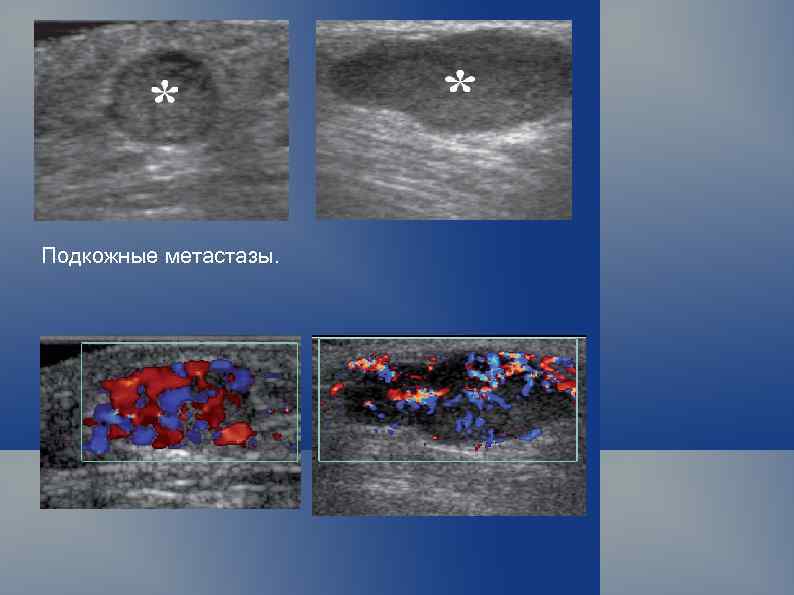

Подкожные метастазы.

Подкожный местастаз меланомы. Редукция кровотока после курса противоопухолевой терапии. Stefano Bianchi · Carlo Martinoli Ultrasound of the Musculoskeletal System, Springer-Verlag Berlin Heidelberg 2007